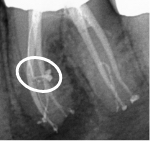

We developed the GentleWave® Technology in pursuit of improving the efficacy and efficiency of root canal treatment (RCT), as well as the patient experience. For well over a century, RCT has depended primarily on files to manually remove infected tissue and tooth structure from inside the tooth. Files, however, have limited reach inside complex root canal anatomy4 and can leave behind infected tissue3 and bacteria, leaving the tooth susceptible to reinfection.

The minimally invasive1 approach of the GentleWave Procedure minimizes manual instrumentation1,3 and instead utilizes a powerful vortex of procedure fluids3 and acoustic energy that cleans the deepest, most complex portions of the root canal system.1,3